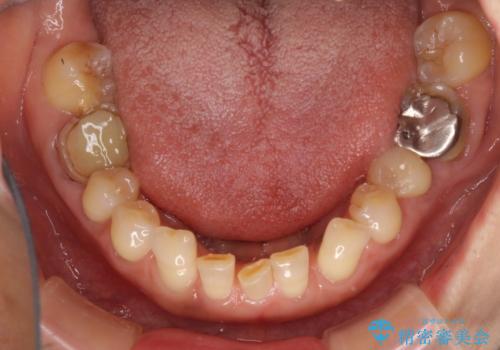

- 割れていると言われて放置してしまった歯や、前歯のデコボコなどが気になるとのことで来院された患者様です。

左上の歯は割れてしまっており、抜歯のうえインプラント治療が必要であり、他にも抜歯の必要な歯がある状態でした。

上顎はほぼ全ての歯をセラミッククラウンにて補綴治療を行う必要があるため、気になるデコボコや深い咬み合わせを改善するために下顎と上顎の臼歯部の矯正治療を行うこととしました。